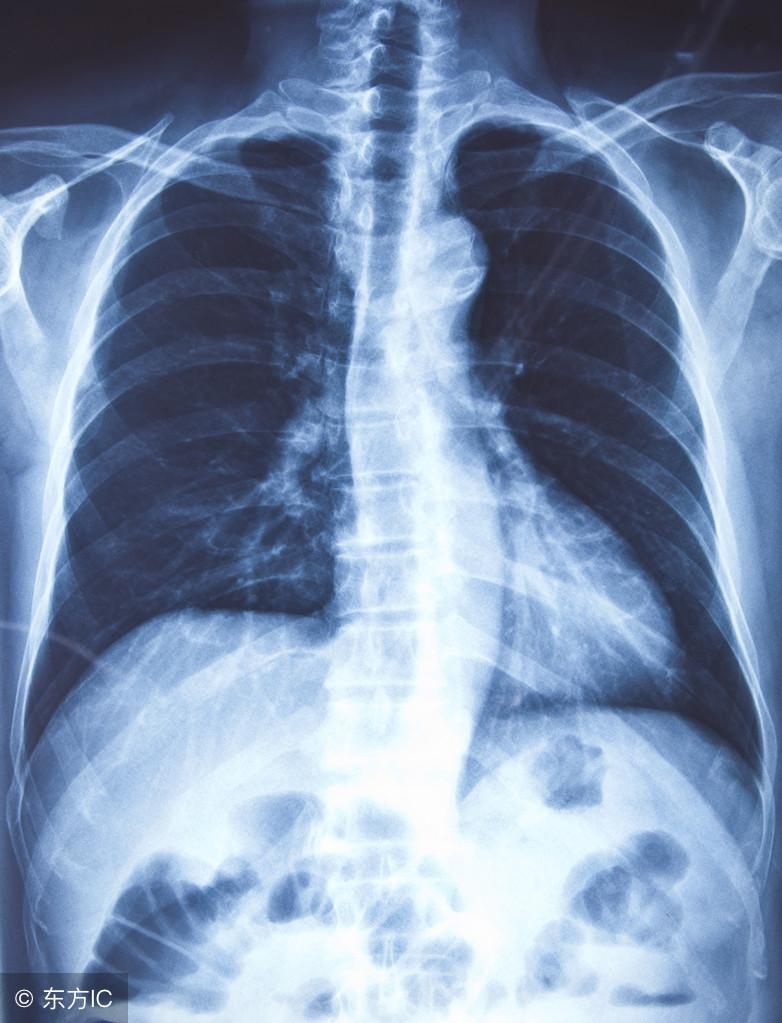

支气管炎蔓延至支气管周围肺组织中可导致支气管肺炎。支气管肺炎患者多表现为寒战、发热,咳嗽增剧,痰量增加且呈脓性。白细胞总数及中性粒细胞增多。X线检查可发现两下肺野有小斑点状或小片阴影。